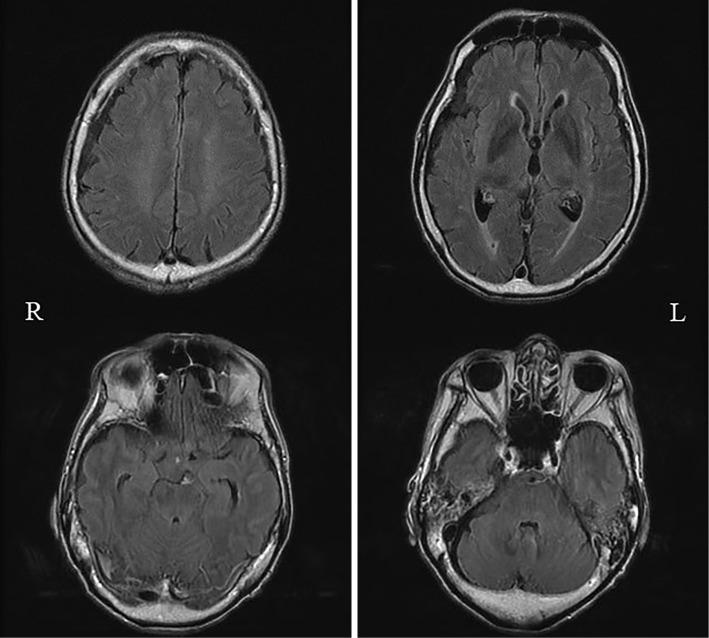

A 74-year-old man experienced diplopia, generalized muscle weakness, and acute respiratory failure. He was diagnosed with Lambert-Eaton myasthenic syndrome (LEMS) and treated with immunotherapy, but no improvement was observed, and additional symptoms, including central apnea and hallucinations, appeared. Subsequent serum and cerebrospinal fluid (CSF) analyses confirmed the presence of GABA receptor antibodies, indicating the coexistence of autoimmune encephalitis. Although there were no findings of malignancy, it is highly likely that occult small-cell lung carcinoma was present. When atypical symptoms occur in patients with LEMS, it is important to consider the possibility of concomitant autoimmune encephalitis.

一位 74 岁男性出现复视、全身肌肉无力和急性呼吸衰竭。他被诊断为 Lambert-Eaton 肌无力综合征(LEMS),并接受免疫治疗,但未见改善,且出现其他症状,包括中枢性呼吸暂停和幻觉。随后的血清和脑脊液(CSF)分析证实存在 GABA 受体抗体,表明同时存在自身免疫性脑炎。虽然没有发现恶性肿瘤的迹象,但很可能存在隐匿性小细胞肺癌。当 LEMS 患者出现非典型症状时,需高度考虑同时存在自身免疫性脑炎的可能性。